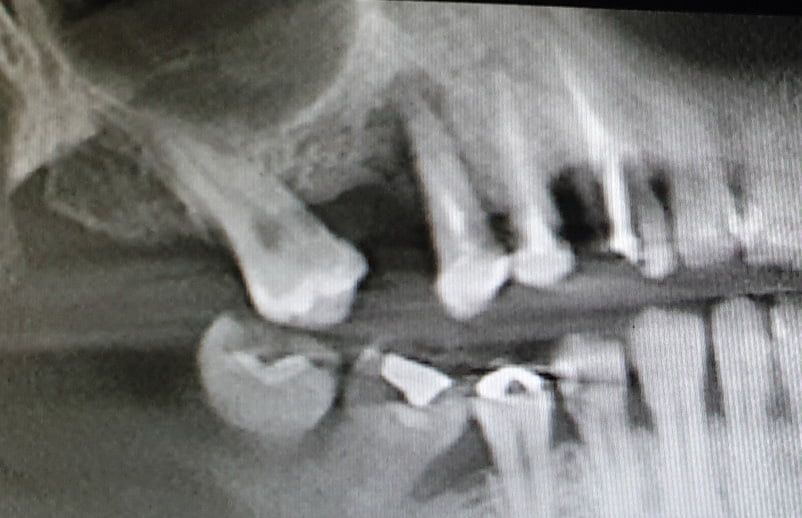

Implant Insertion Socket Type III & Pneumatized Maxillary Sinus

Dr. ABDUSALAM E. ALRMALI Country: Libya Gallery Patient’s Data: Age: 48 Sex: Female Smoker: No Pathologies: None Hygenic state: Good Alergies: None We inserted a wide implant in a difficult risky case with socket type III & pneumatized maxillary sinus where the primary stability difficult to achieve.We decide to for an immediate placement with ossodensification […]